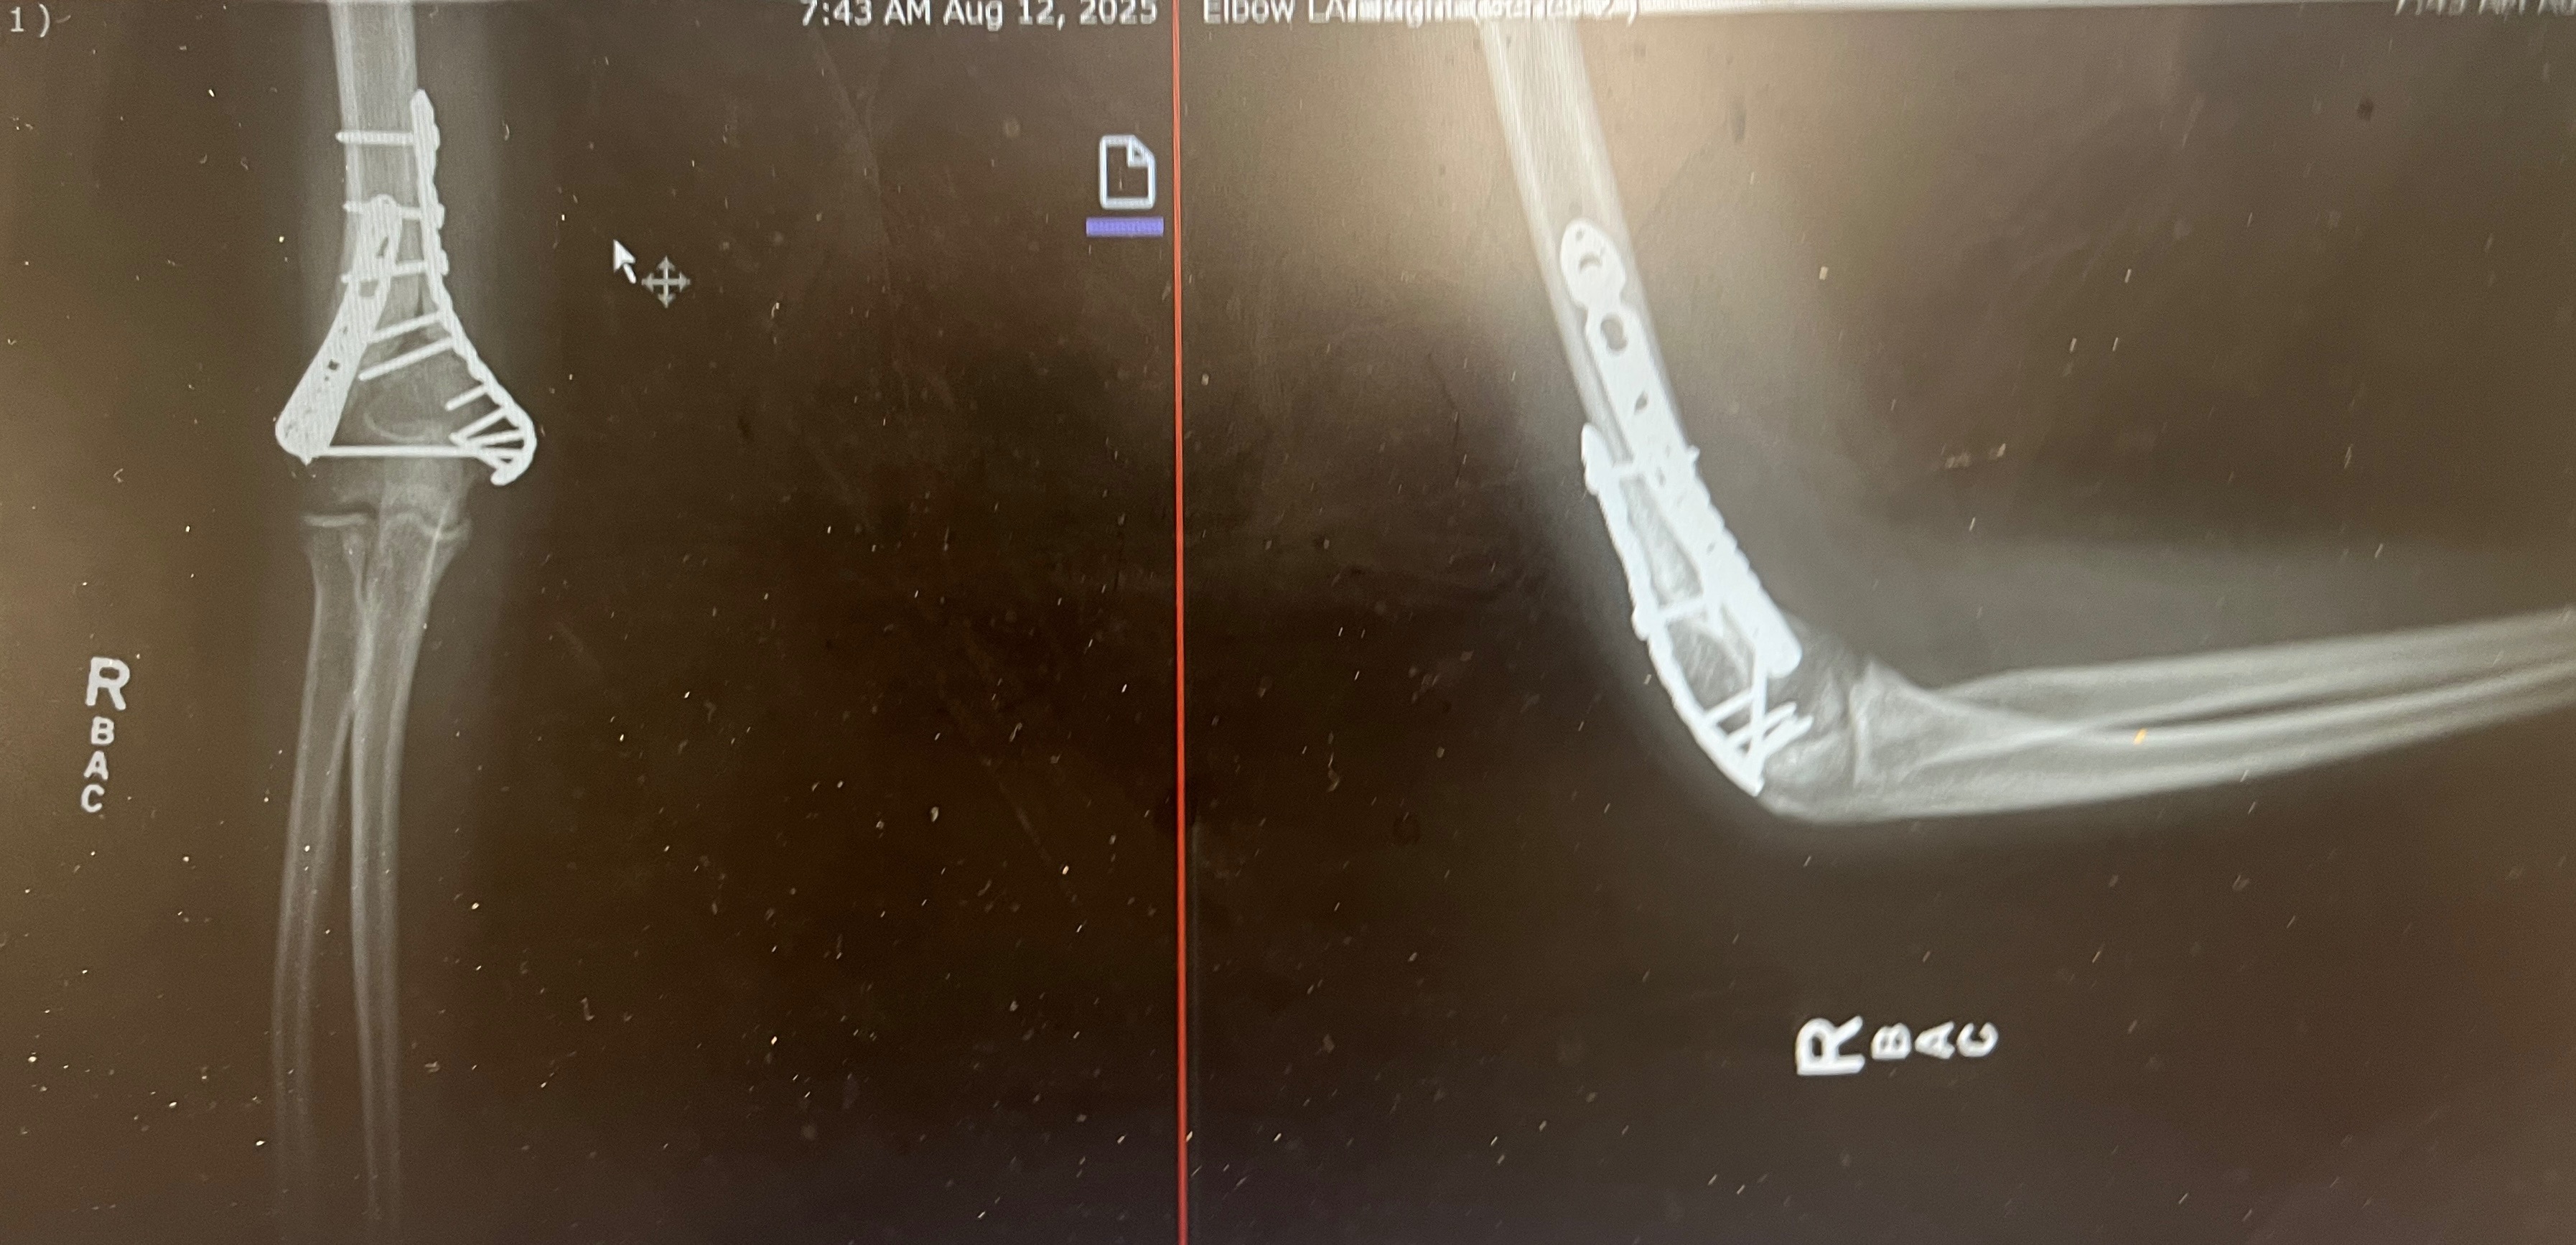

i’m adam, an artist and barista. earlier this summer I got in a bad bicycle accident and broke my arm severely. I am currently in occupational therapy to regain strength while my bones continue to heal, but I have been out of work for two months and probably for another while I regain mobility. I also have my art available for sale, but I am grateful for any assistance. your donation will help cover rent and food costs and expenses for my dog until i’m able to return to work. thank you